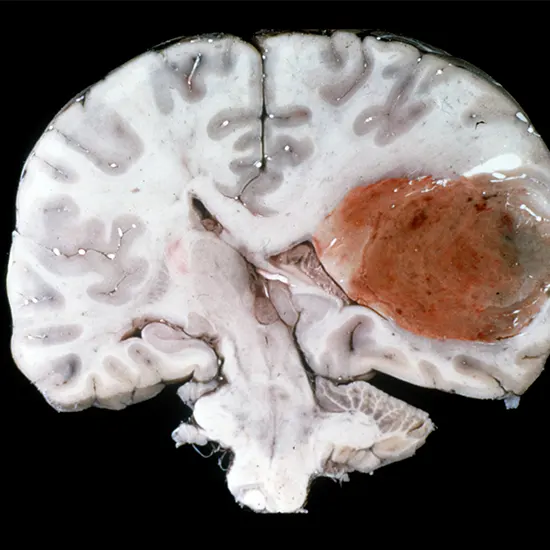

Glioblastoma (GBM) is a kind of most important brain tumour that is regarded as one of the most aggressive and lethal types of cancer. It is categorized as a grade IV astrocytoma and is responsible for about 15% of all foremost Brain tumours.

GBM generally develops from cells known as astrocytes, which are supportive cells in the brain. The tumour cells in GBM are invasive and can develop rapidly, spreading shortly into close intelligent tissue. This makes it hard to dispose of the tumour through surgery.

Glioblastoma is a kind of cancer that develops in the brain. It is the most aggressive and lethal shape of glioma, a kind of foremost intelligence tumour that originates from glial cells, which supply aid to neurons.

Glioblastoma tumours are additionally acknowledged as grade IV astrocytoma, which means they are the most malignant and hastily developing kind of astrocytoma.

Glioblastoma tumours are characterized by their capacity to develop and unfold rapidly at some stage in the brain. They can infiltrate wholesome Brain tissue and shape new blood vessels to grant the tumour with vitamins and oxygen.

This invasiveness makes it very hard to dispose of the tumour via surgery.

- GBM tumours originate from glial cells, which are supportive cells that furnish structural aid and nourishment to neurons in the brain. In GBM, these glial cells emerge as strange and start to develop and divide uncontrollably, forming a mass of cancerous cells. One key attribute of GBM is its potential to invade and infiltrate healthful Brain tissue.

- GBM cells can secrete enzymes that smash down the extracellular matrix, which is a community of proteins and different molecules that help shape the brain. This lets GBM cells migrate close by healthy tissue and structure new tumours, making it very hard to absolutely eliminate most cancers via surgery.

- Another necessary characteristic of GBM is its capacity to generate new blood vessels to furnish the tumour with vitamins and oxygen. GBM cells can produce proteins that promote angiogenesis, or the increase of new blood vessels, permitting the tumour to develop and spread all through the brain.